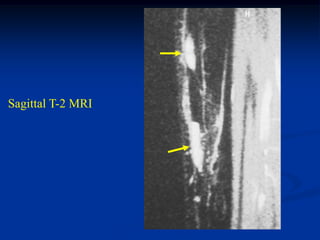

Case #1105

54 year male with

chordoma C-spine